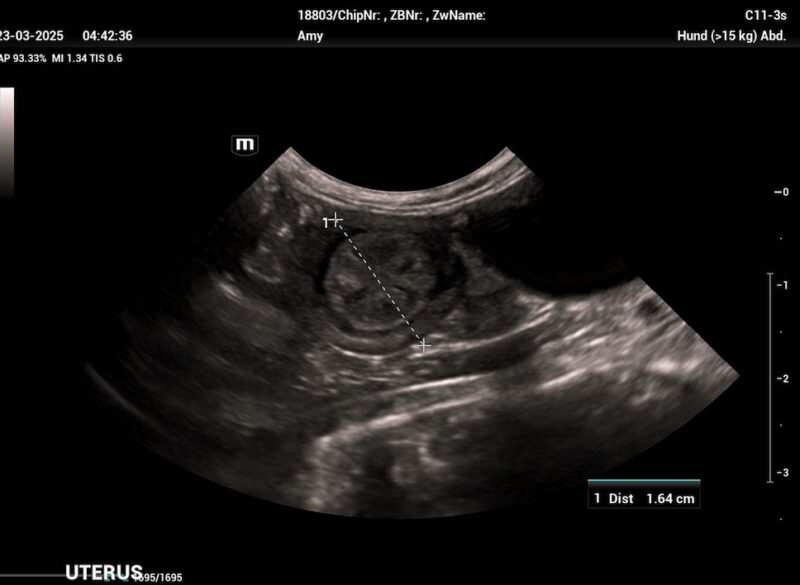

Die Uterusinvolution ist, verglichen mit anderen Spezies, beim Hund ein langsamer Prozess und kann je nach Studie 12 bis 15 Wochen dauernd. Die meisten Rückbildungsvorgänge finden in den ersten 4 bis 6 Wochen post partum statt und in dieser Zeit zeigt die Hündin auch einen geruchlosen, anfangs grünlichen (aufgrund des Uteroverdins der Plazenta) dann eher dunkelroten bis braunen vaginalen Ausfluss, der im Laufe dieser Wochen kontinuierlich abnimmt. Mit diesen Lochien werden Teile der Gebärmutterschleimhaut abgebaut, die aufgrund des epitheliochorialen Aufbaus der Plazenta beim Hund erneuert werden müssen.

Sollen bei der Geburt nicht alle Plazenten vollständig gesehen worden sein, empfiehlt sich immer eine Kontrolle mittels Vaginoskopie und Ultraschall. Sind Ganze oder auch nur Teile davon im Uterus verblieben und nicht vaginal zu entfernen, kann auch hier Oxytocin gegeben werden um die Uteruskontraktionen und somit die Ablösung der Plazenta zu fördern. (1-(3) I.E. 2-3 mal täglich (Arnold 2000a)). Innerhalb der ersten Tage nach der Geburt sinkt jedoch die Oxytocinrezeptorexpression im Myometrium bereits rapide ab, sodass eine längere Gabe oft nicht den gewünschten Erfolg bringt. Gleichzeitig sollte man eine gute Breitbandantibiose (bei säugenden Hündinnen meist Amoxicillin/Clavulansäure) und im Bedarfsfall auch ein Nicht-steroidales Antiphlogistikum verabreichen. Sollte sich die Plazenta nicht lösen, muss sie vom Körper resorbiert und die Hündin somit weiterhin engmaschig überwacht werden. Im schlimmsten Fall kann auch hier eine OP nötig werden.